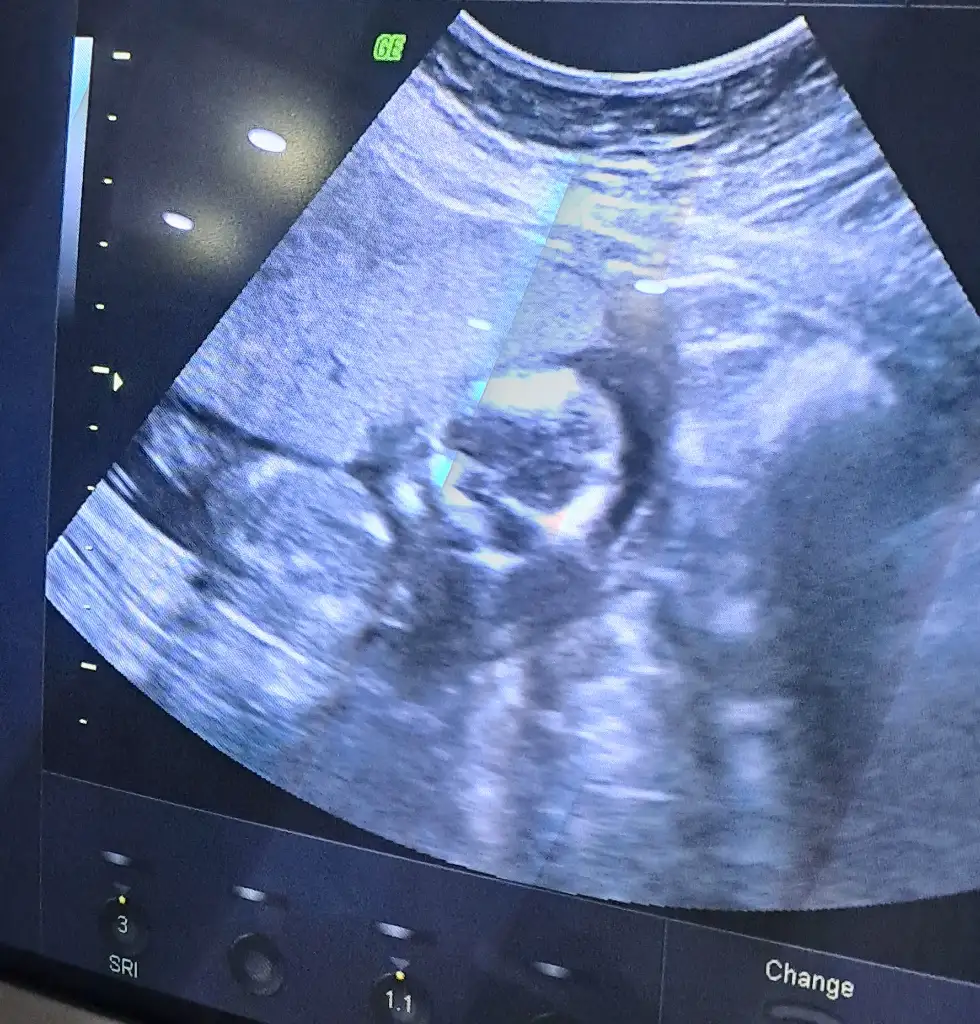

8+3 karından ultrasonla çekildi cinsiyet tahmini yapabilecek var mı acaba

Eklentiler

• IMG_20250613_141906.webp

IMG_20250613_141906.webp

17,3 KB · Görüntüleme: 73

Erkektir o zaman 😊

Hayırlısı mübaregi olsun sağlıkla gelsin önce yavrucak erkek kız hiç farketmez elbette ama üç oğlan dan sonra bir kız insan istiyor tabi 😊 Ama dediğim gibi önce sağlık sıhhat sonrası kısmet Rabbim güzel yetiştirmeyi nasip eylesin 🤲🏻